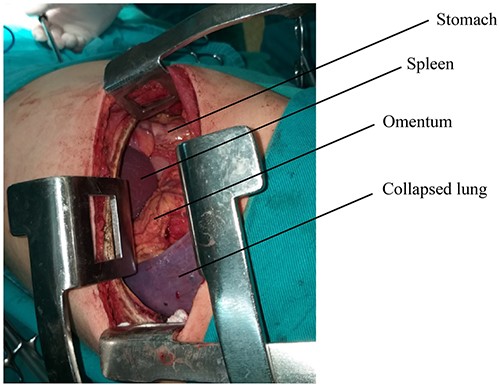

The surgical procedure was performed under general anesthesia with double-lumen tube and high airway pressure with low ventilation. Left lung was isolated, and a left lateral thoracotomy through the seventh intercostal space was performed. The spleen, stomach, omentum and part of the colon were found in the left chest, as shown in Fig. 3.

The diaphragm, which was found torn in its muscular section, was reached, and the abdominal viscera was returned to the abdomen. The diaphragm was then repaired, and the left lung was well disseminated (Fig. 4).